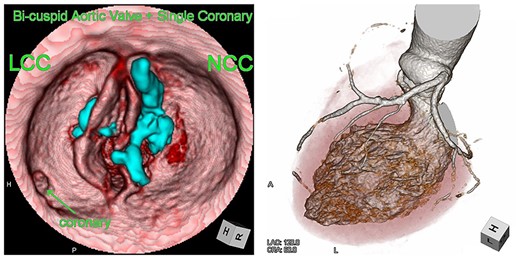

Computed tomography images of calcification before (red) and after (blue) TAVR. Distorted THV (green) at the annulus level was noted. Images were merged to detect the shifting calcification.

Postoperative echocardiography revealed a high transprosthetic gradient as well as moderate PVL. Alternatively, multidetector computed tomography (MDCT) revealed THV migration, tilted and elevated around the NCC annulus (Fig. 3). MDCT also identified the calcification location before and after TAVR (Fig. 2). Those two different calcification locations were merged into one image to clarify the shifting calcification. The calcification was shifted considerably around the NCC area of the annulus, consistent with the migration area of THV.